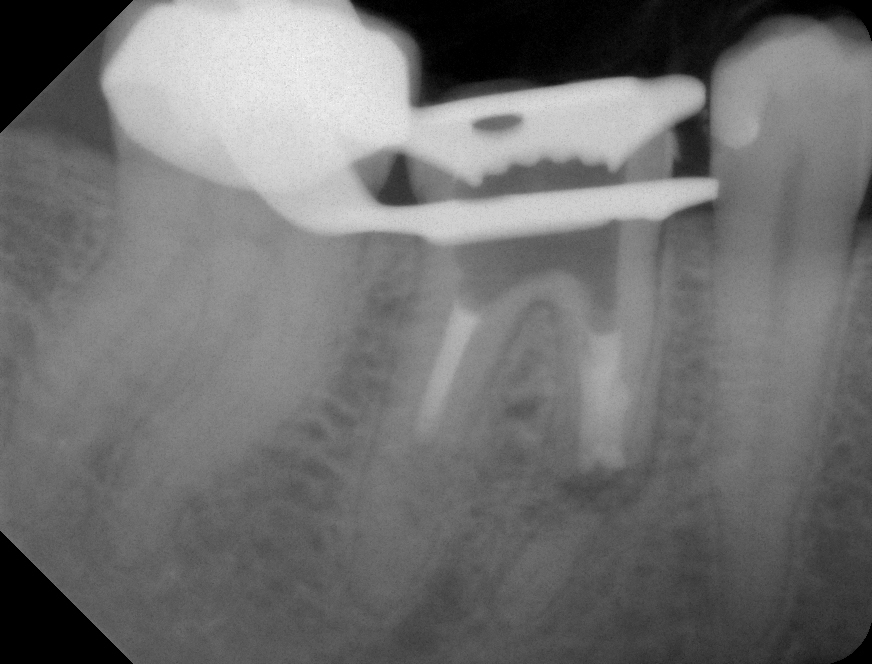

06 – Zahn 46 – WF mit MTA – orthroradial Veröffentlicht 2. Juli 2013 am 872 × 664 in Wurzelresorption mal anders